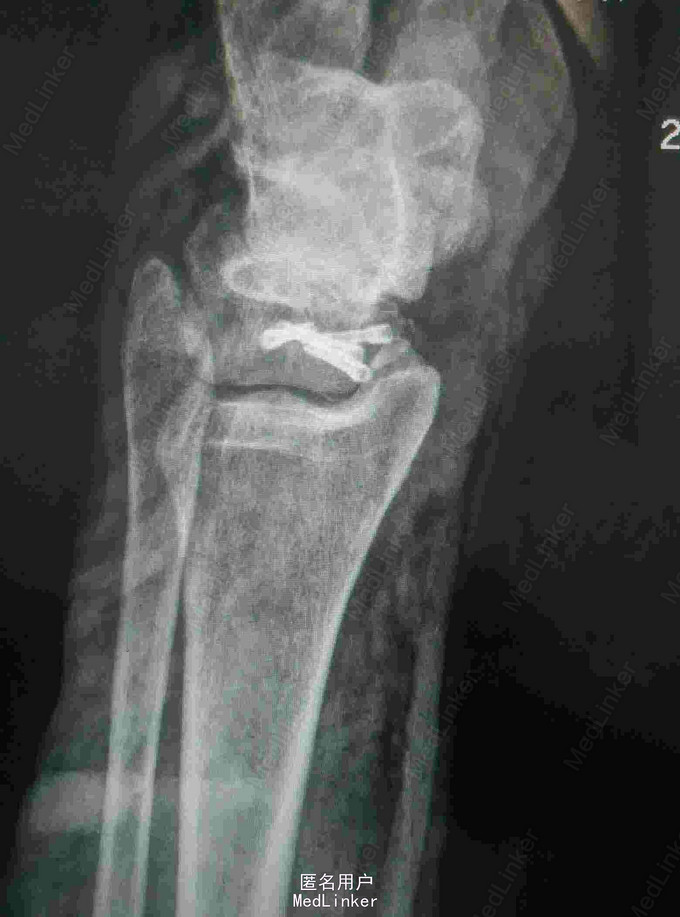

查体:左踝关节肿胀明显,局部皮肤压痛,无皮损及皮下淤斑,踝关节活动受限,各足趾感觉正常,足背动脉搏动存在。 辅查:我院CT提示距骨、足舟骨、跟骨骨折

诊断:左足距骨、足舟骨、跟骨骨折 治疗:距骨骨折切开复位内固定术

随访:石膏固定4-6周,3月内禁止负重,定期复查。 讨论:患者X线片对左足骨折显示不够清楚,基本常规行CT,可以看到明显的距骨骨折,累及关节面,需手术复位关节面。足舟骨以及跟骨骨折未明显移位保守处理。